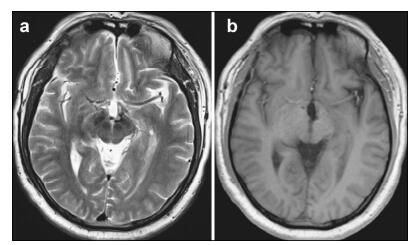

Postoperatively, the patient reported no further visual acuity or field deficits. However, he presented with a temporary electrolyte disorder characterized by fluctuation in the concentration of serum sodium. After fluid replacement therapy and oral hormone supplementation, he recovered well, without any neurological deficits. Postoperative MRI revealed com plete excision of the CM without destruction of the surrounding structures. The two years of follow-up found change in visual acuity or CM recurrence on MRI (Figure 3).

| Figure 3 Magnetic resonance imaging (MRI) of the postsurgical hypothalamic cavernous malformation at two-year follow-up. Axial section of T2-weighted (a) and gadolinium-enhanced T1-weighted (b) MRI reveals the complete removal of the hypothalamic cavernous malformation and no evidence of recurrence or rebleeding. |